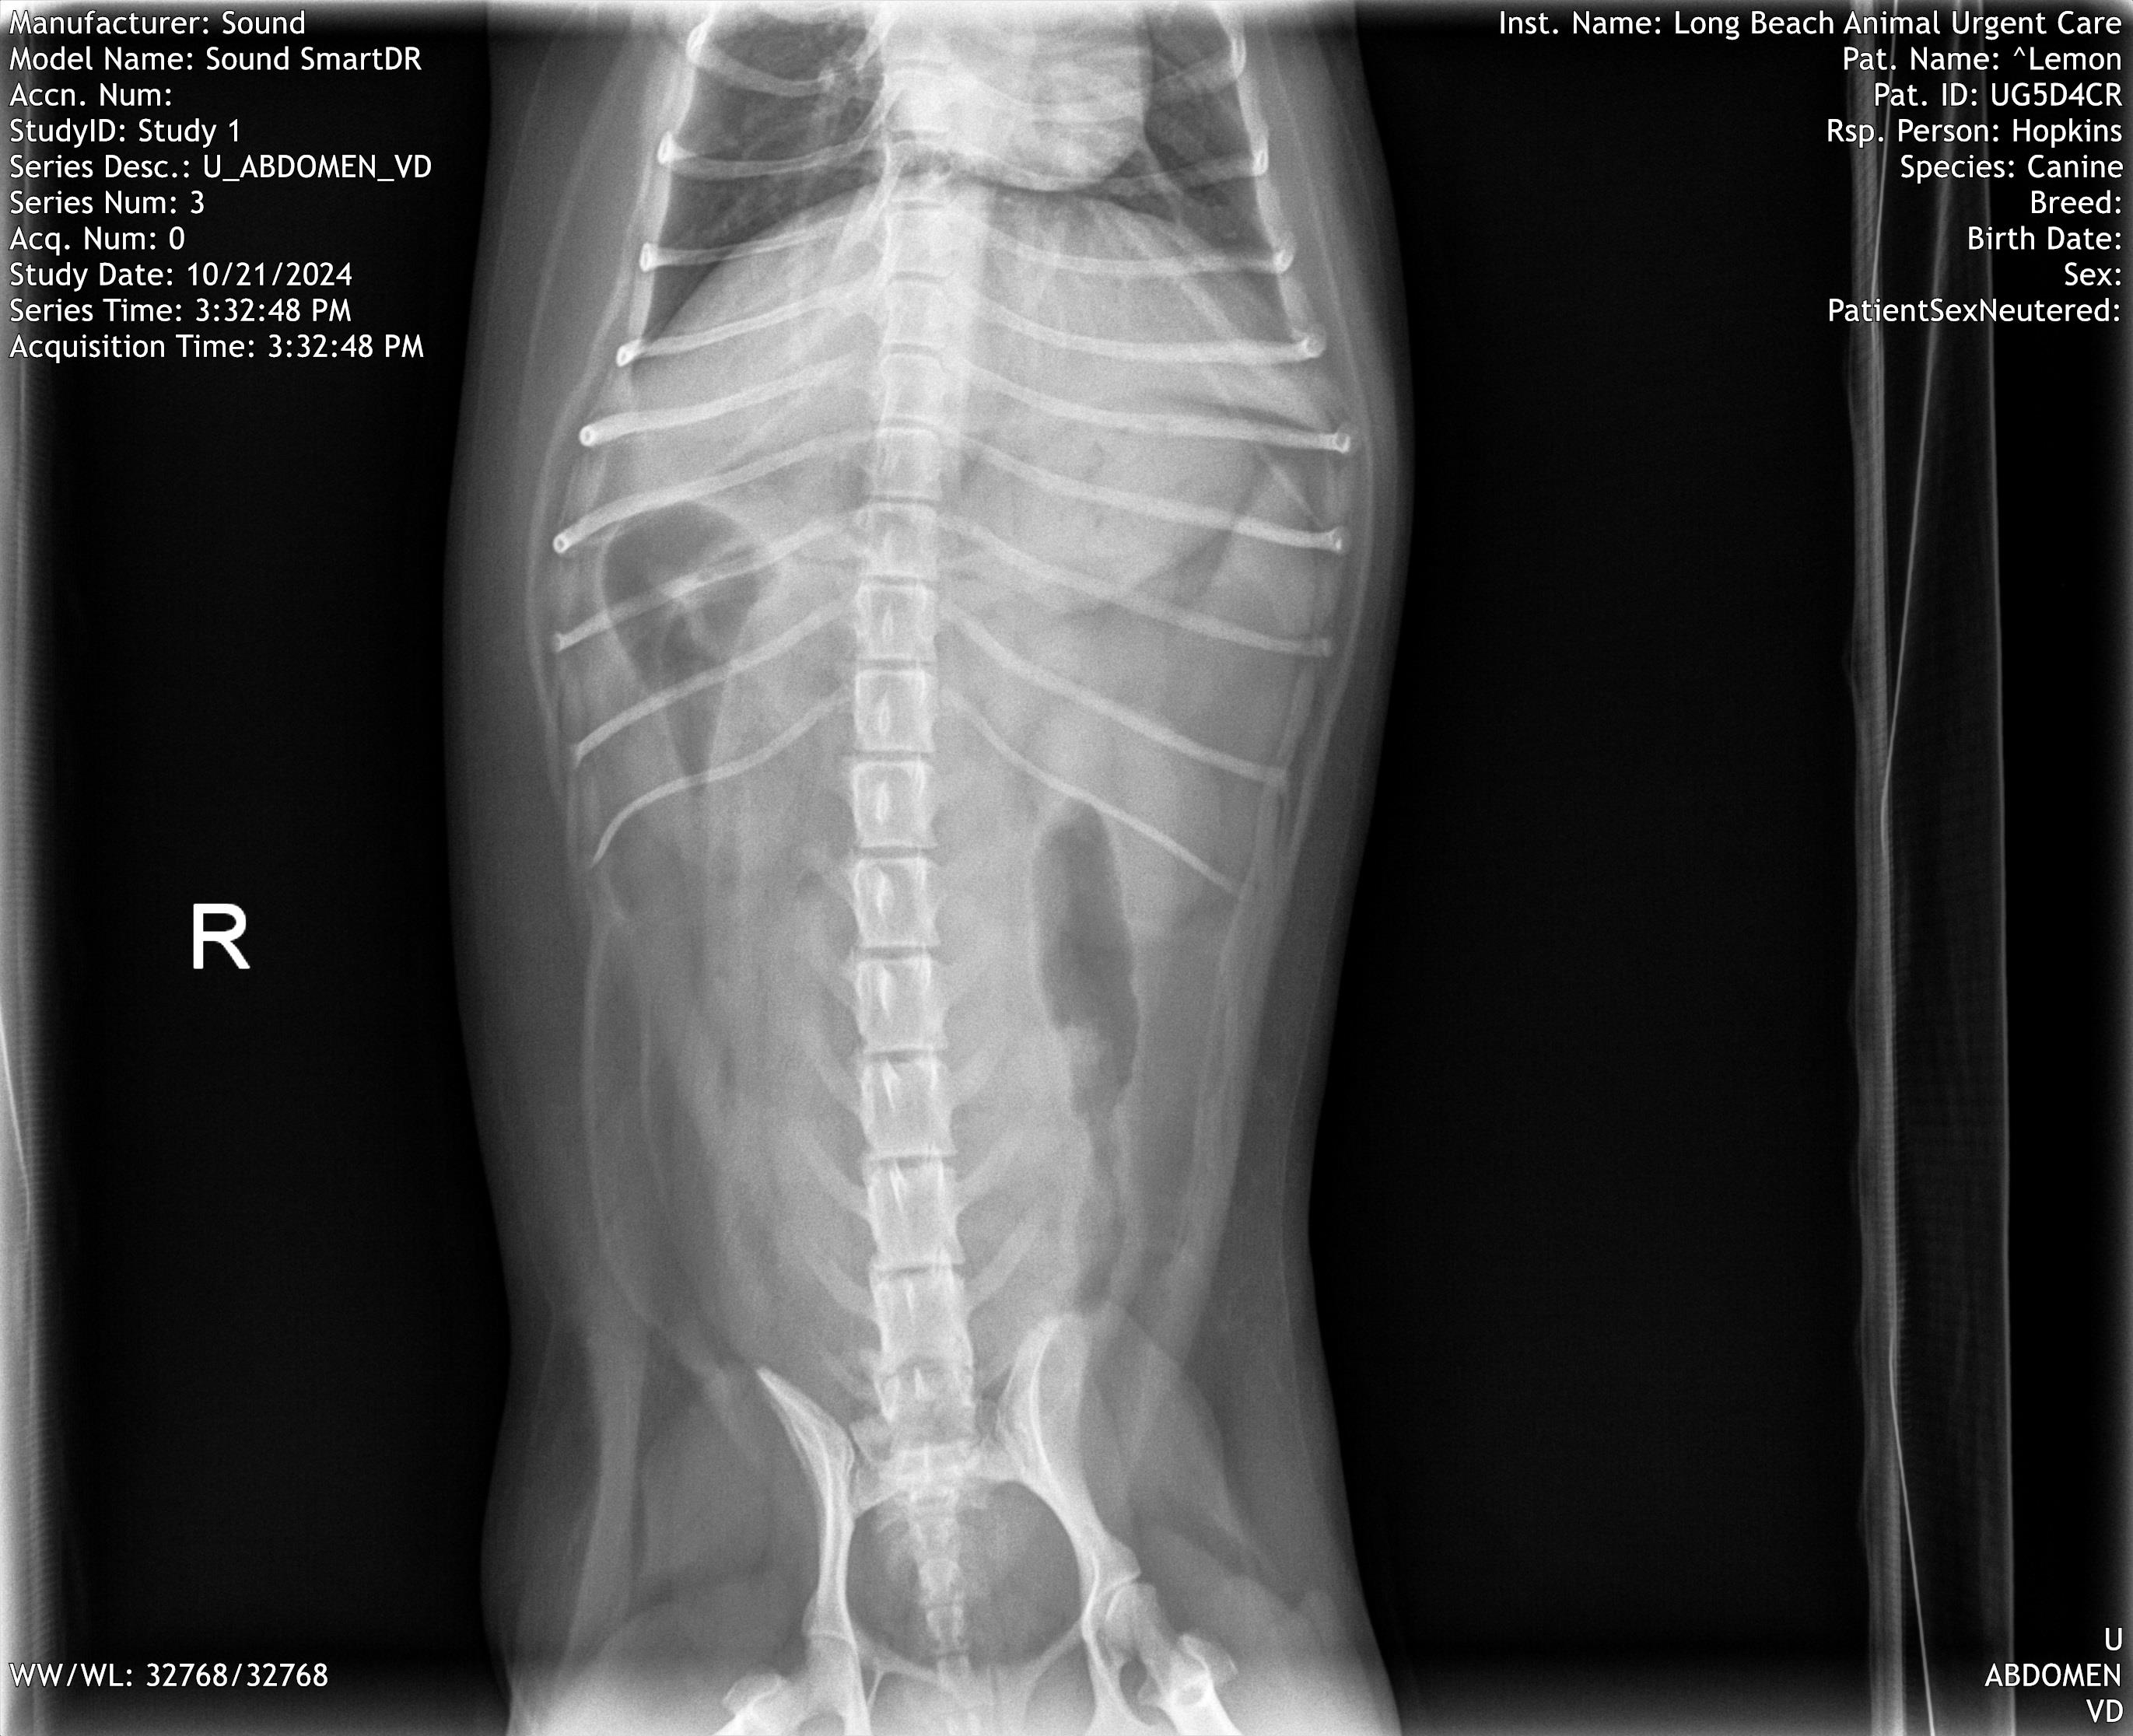

I was able to get Lemon to the urgent care on Monday, where an X-ray and bloodwork indicated that her gastrointestinal issues were likely the result of bacteria rather than a foreign object. While this ruled out the need for emergency surgery, my girl was extremely dehydrated and in need of antibiotics and anti-nausea medication.